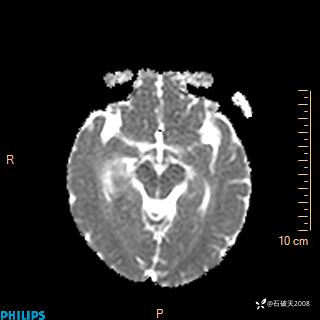

DWI